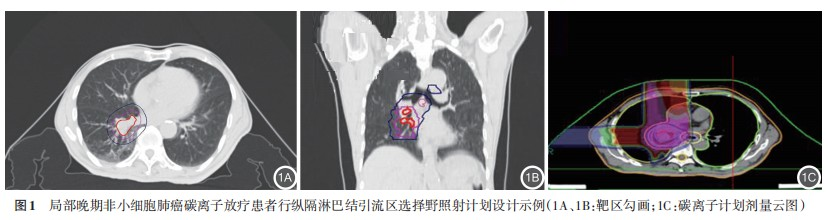

2. Treatment Outcomes: According to the study design, both groups received 48 Gy (RBE) to the lymph node drainage area, but with different fractionation schemes: 3 Gy (RBE) × 16 fractions in Group A and 4 Gy (RBE) × 12 fractions in Group B. The treatment plan design is shown in Figure 1. To evaluate dose distribution to organs at risk (OARs), we conducted statistical analysis of relevant dosimetric parameters. The results showed no statistically significant differences between the two groups in the following parameters: GTV volume, CTV volume, mean lung dose (Dmean), V5 Gy(RBE), V20 Gy(RBE), and V30 Gy(RBE) of the ipsilateral lung; V20 Gy(RBE), V30 Gy(RBE), and Dmean of the heart; V30 Gy(RBE), V50 Gy(RBE), maximum dose (Dmax), and Dmean of the esophagus; Dmax of the trachea; and Dmax of the spinal cord (all P>0.05). Detailed data are presented in Table 2.